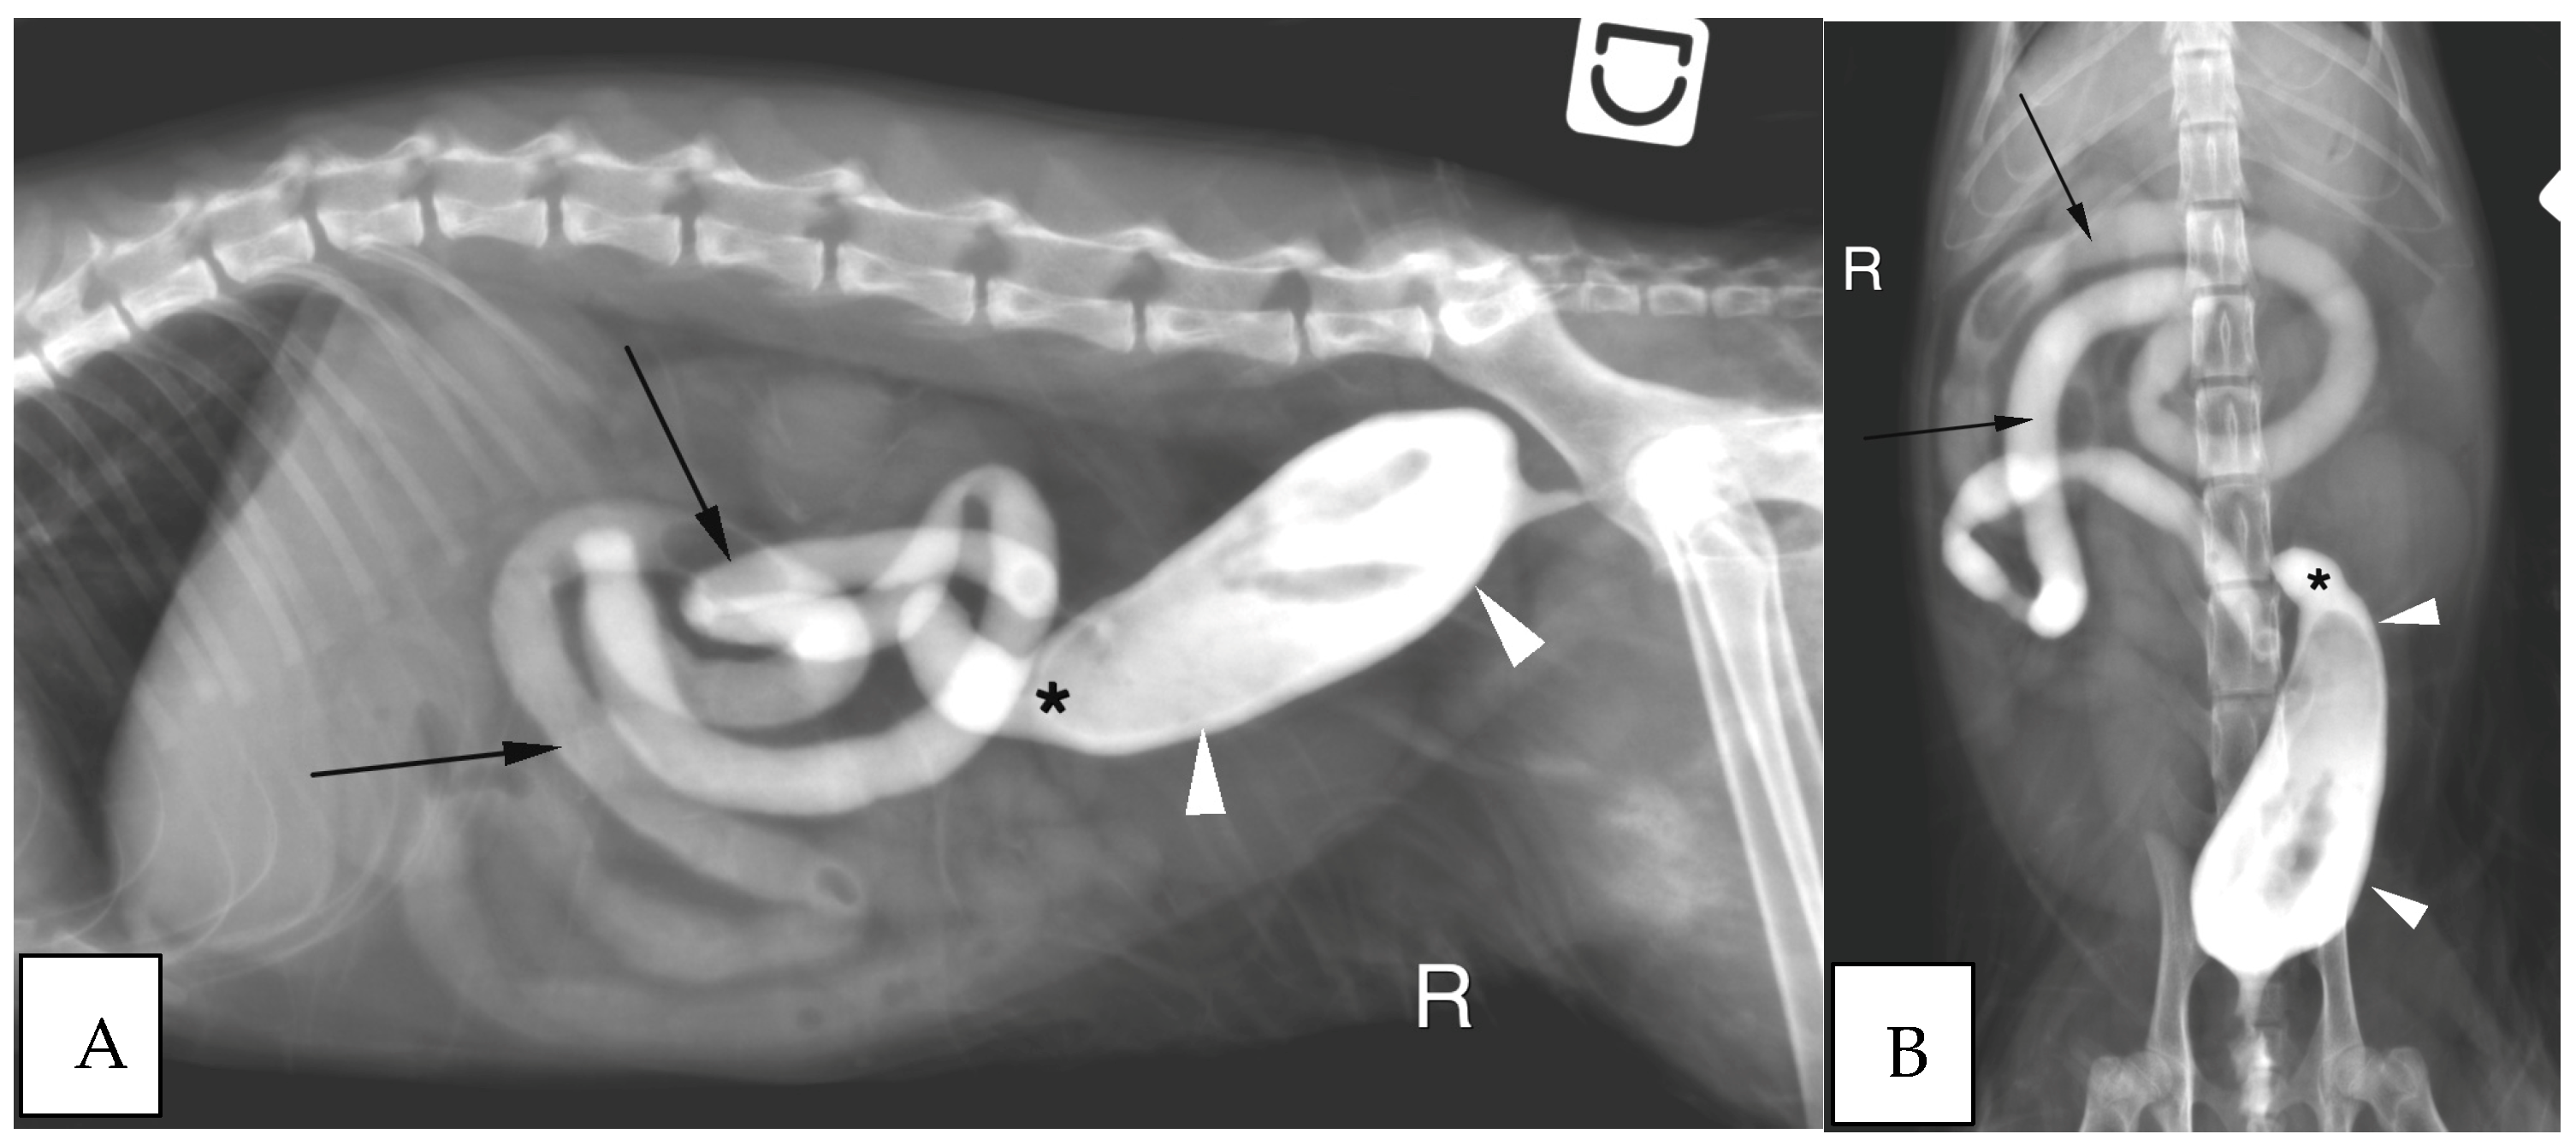

3.2.3. Abdominal Radiographs